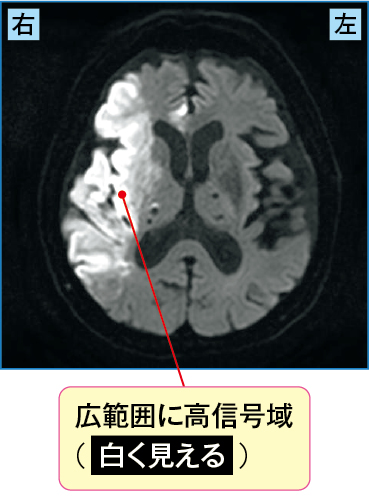

突然の意識障害が出現したため、家族が救急要請して搬送されてきた患者さんの例です。

すぐにCT(図2-1)が撮影され、右中大脳動脈領域において低吸収域を示していました。そこで脳梗塞が疑われMRIを施行し(図2-2)、その結果、DWIでは広範囲に高信号域を、ADCmapでは低信号域を認め、またT2強調像においても高信号域が認められました。

発症後、数時間が経過している急性期の右中大脳動脈領域の心原性脳梗塞と診断され、ヘパリンの投与が開始されました。

図2-1 急性期の心原性脳梗塞のCT画像

図2-2 急性期の心原性脳梗塞のMRI(DDWI、拡散強調像)